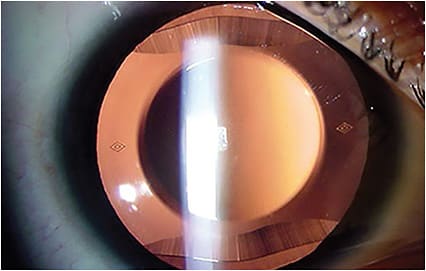

AS-OCT images depicting adequate vaults (250 μm and 740 μm, respectively) of an ICL over the natural crystalline lens.IMAGE COURTESY KATHRYN HATCH, MD

- Prevention of pupillary block with the Visian ICL. Two large peripheral iridotomies, typically made at 10 o’clock and 2 o’clock, should be made preoperatively or intraoperatively to prevent pupillary block. Additionally, careful note should be taken of ideal ICL vault, typically measured relative to corneal thickness. Optimal vault is 0.75 to 1.5 corneal thickness on slit lamp examination, approximately 250 μm to 750 μm.10